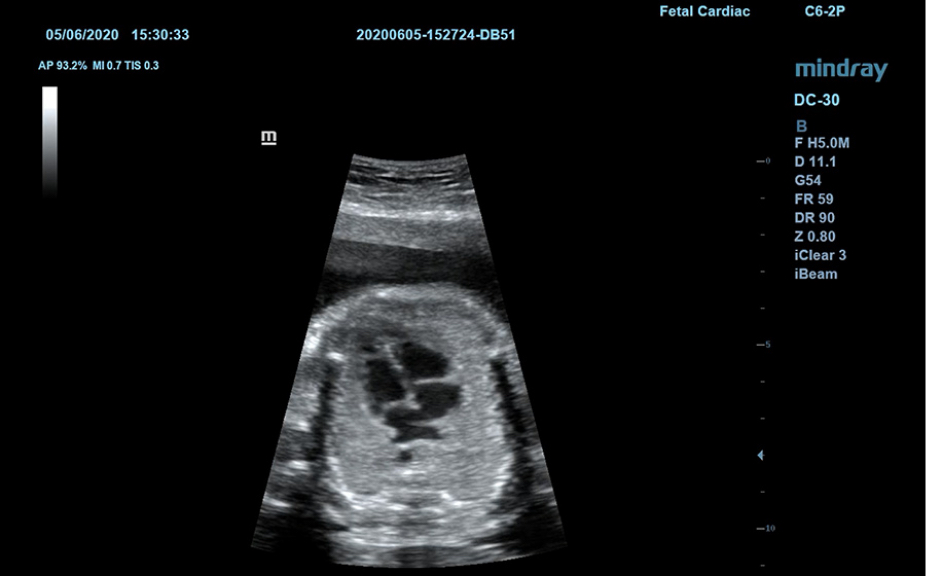

Ilustraciones anatĂłmicas normales que incluyen imĂĄgenes esquemĂĄticas y ecogrĂĄficas.

VisualizaciĂłn lateral de ultrasonografĂas estĂĄndares que proporciona orientaciĂłn visual sobre la regiĂłn de interĂ©s.

ImĂĄgenes de ecografĂas estĂĄndares

3

ComparaciĂłn de ecografĂas en tiempo real para su referencia.

ImĂĄgenes de ecografĂas de referencia

ImĂĄgenes clĂnicas